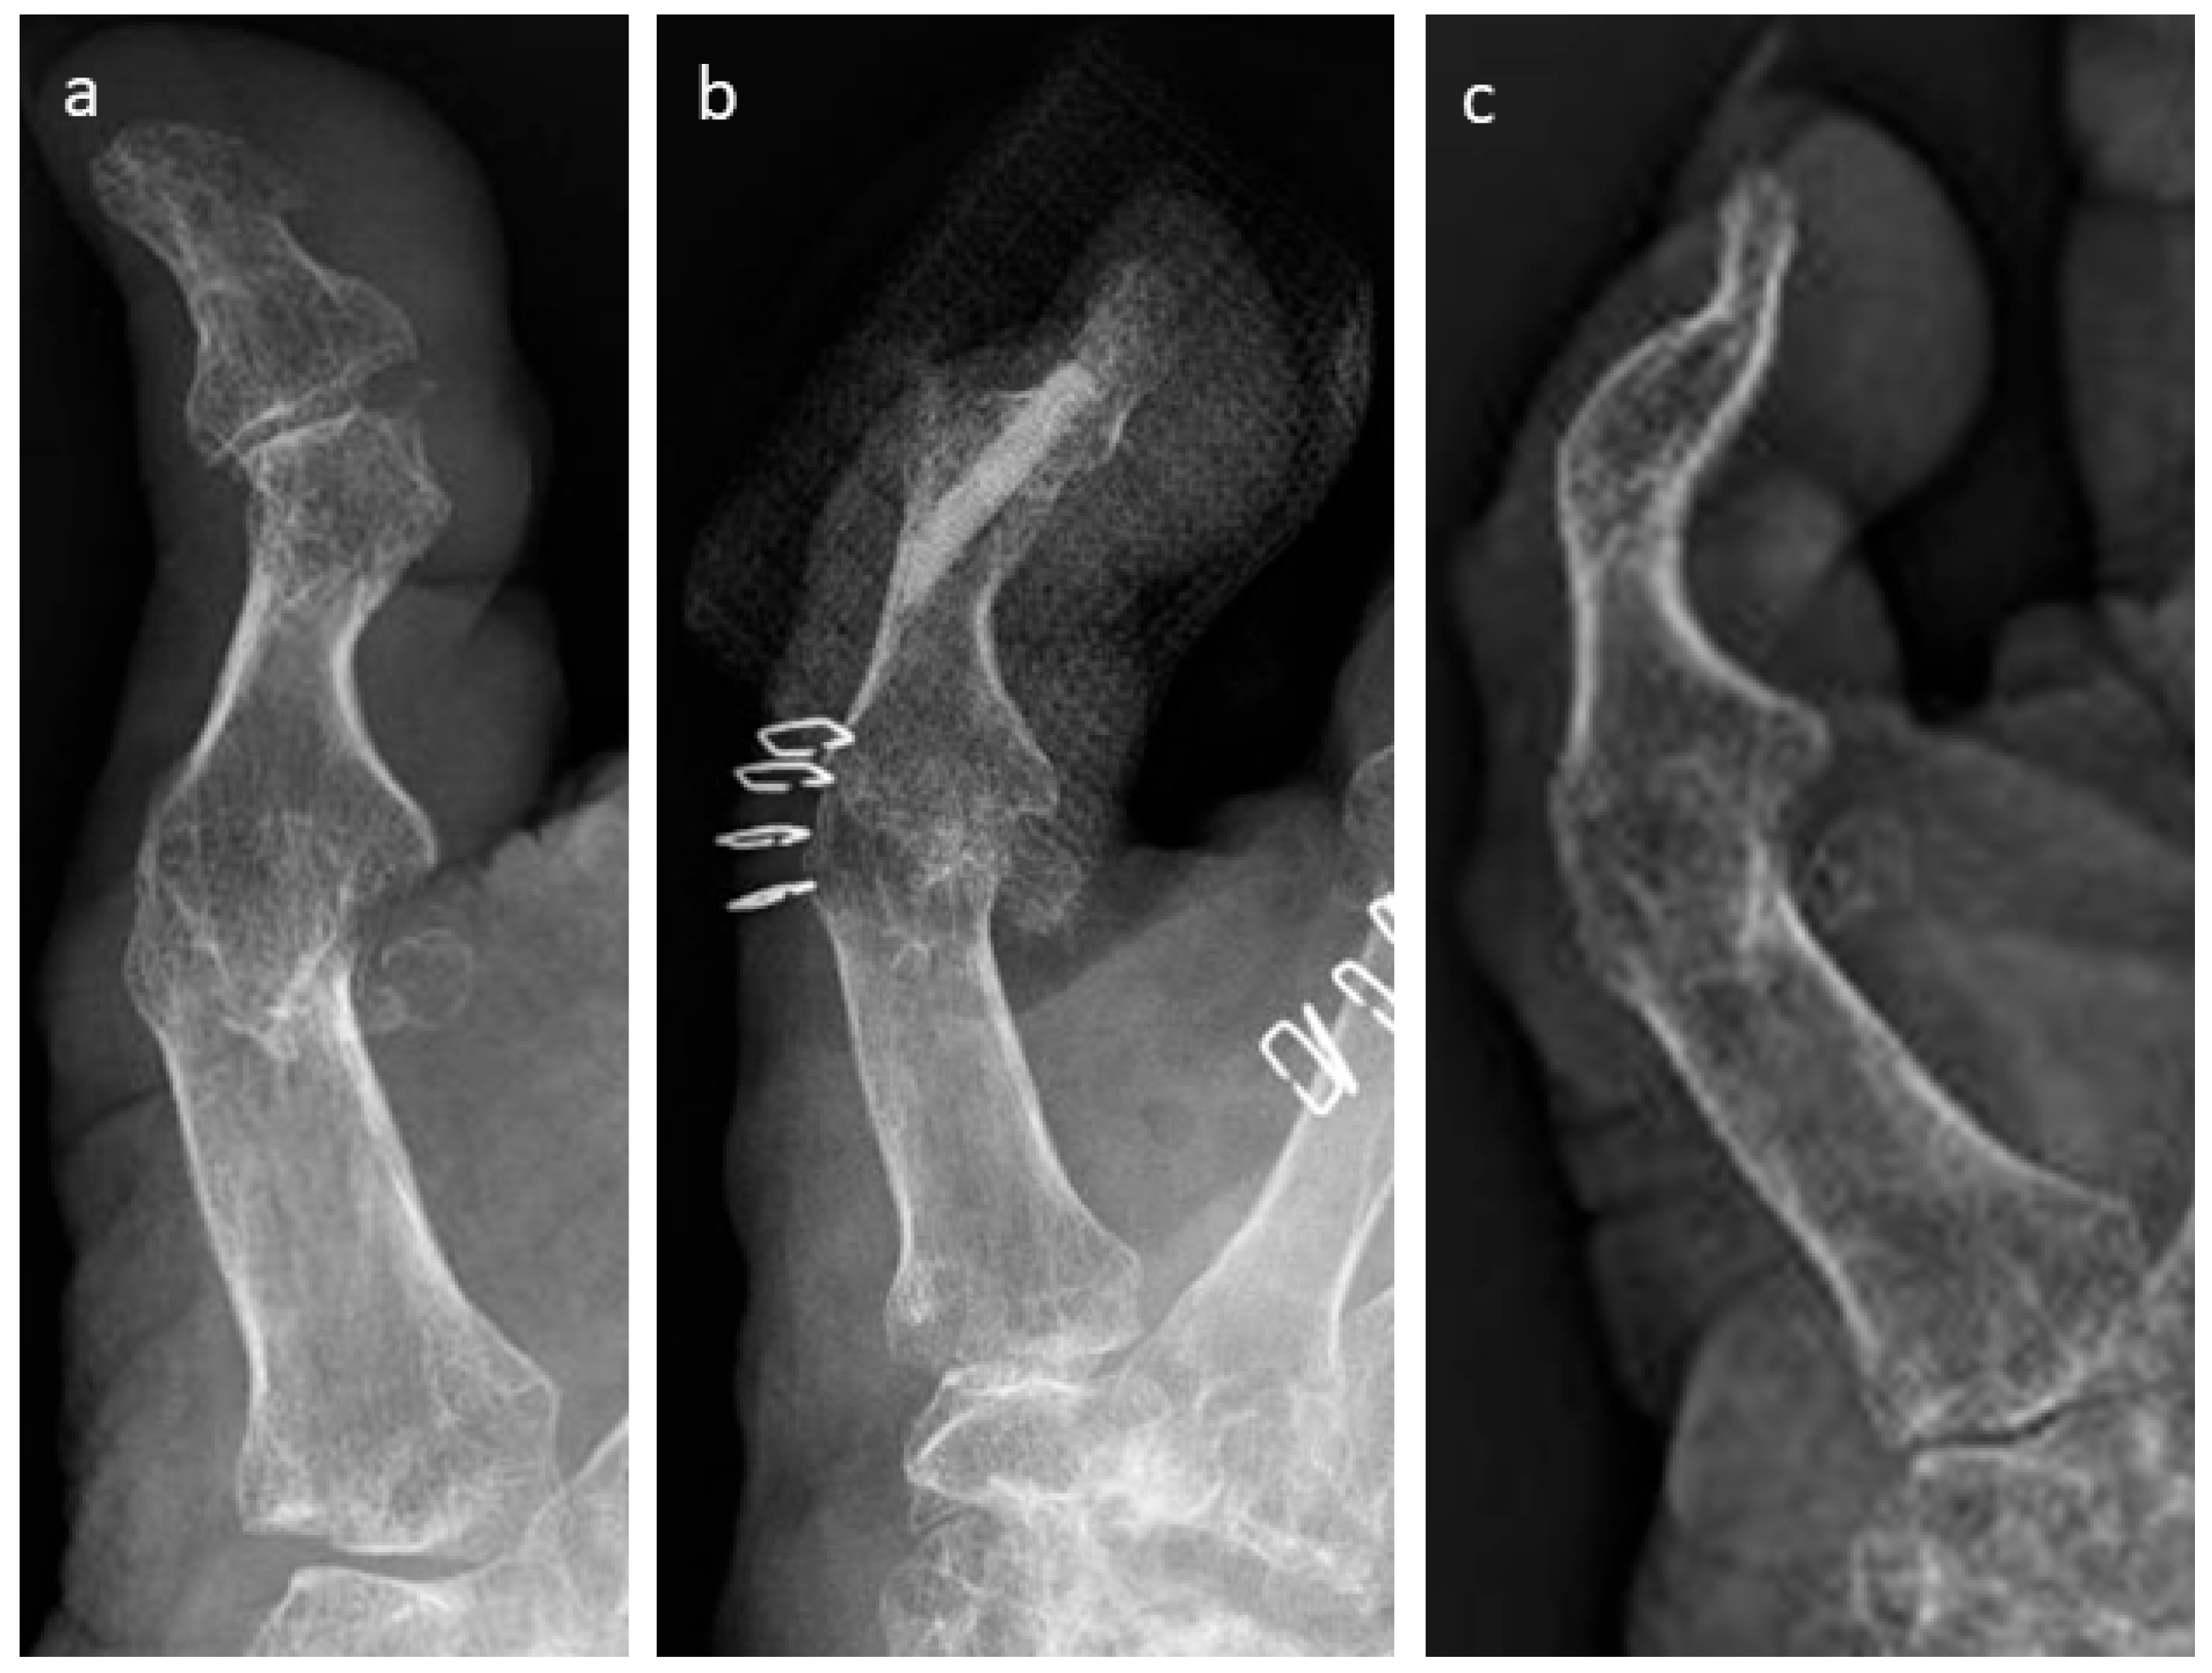

3.4. Selected Case Descriptions